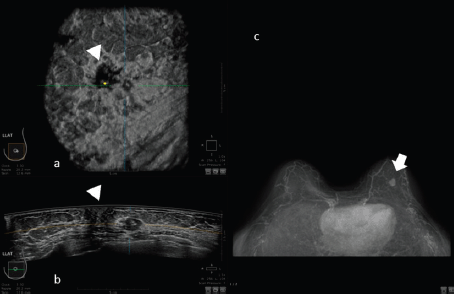

For example, in the study of Schmachtenberg [44], 3D ABUS correlates well with MRI and histopathological measurements. An example of this correlation is shown in Figure 4.

Figure 4. 50-year-old patient with biopsy proven left breast carcinoma. a: 3D ultrasound (ABUS) image at the dedicated workstation. Reconstructed coronal plane: the lesion is marked as a reference point. The nipple is marked with the arrowhead. b: 3D ultrasound (ABUS) image at the dedicated workstation. Reconstructed axial plane: the lesion is marked as a reference point. c: Breast MRI: the lesion is marked with the arrow.